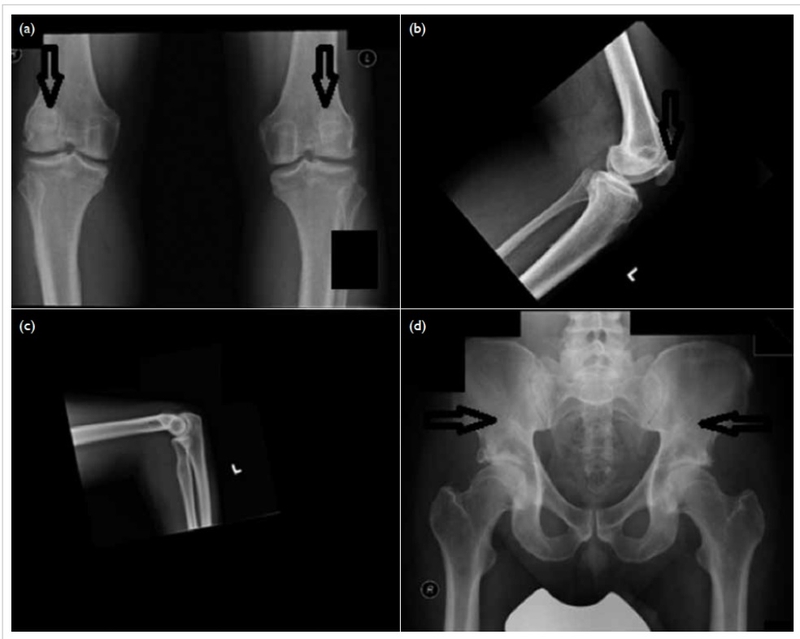

Người mắc hội chứng móng và xương bánh chè thì có móng tay và móng chân phát triển không đều. Móng tay và móng chân có thể có hoặc không, hoặc có thể có màu đục. Ngoài ra còn có các bất thường ở xương bánh chè. Trong đó có thể có xương bánh chè có thể gặp các vấn đề như: Thiểu sản hai bên, trật khớp đầu quay, không có xương bánh chè,...

Ngoài ra người bệnh còn có thể có các dấu hiệu như: Vẹo cột sống, cử động khuỷu tay hạn chế, đầu gối không vững, tăng nhãn áp, tăng huyết áp,... Các triệu chứng trên móng và xương bánh chè thể hiện rõ ngay từ khi sinh ra. Các triệu chứng khác sẽ biểu hiện vào những năm trưởng thành.

Để chẩn đoán hội chứng móng và xương bánh chè, bác sĩ sẽ đánh giá trên lâm sàng. Các đánh giá bao gồm: Đánh giá khả năng vận động của các khớp, kiểm tra độ mở rộng cơ và khớp, đánh giá khả năng vận động chung,... Một số chỉ định cận lâm sàng có thể kèm theo như: